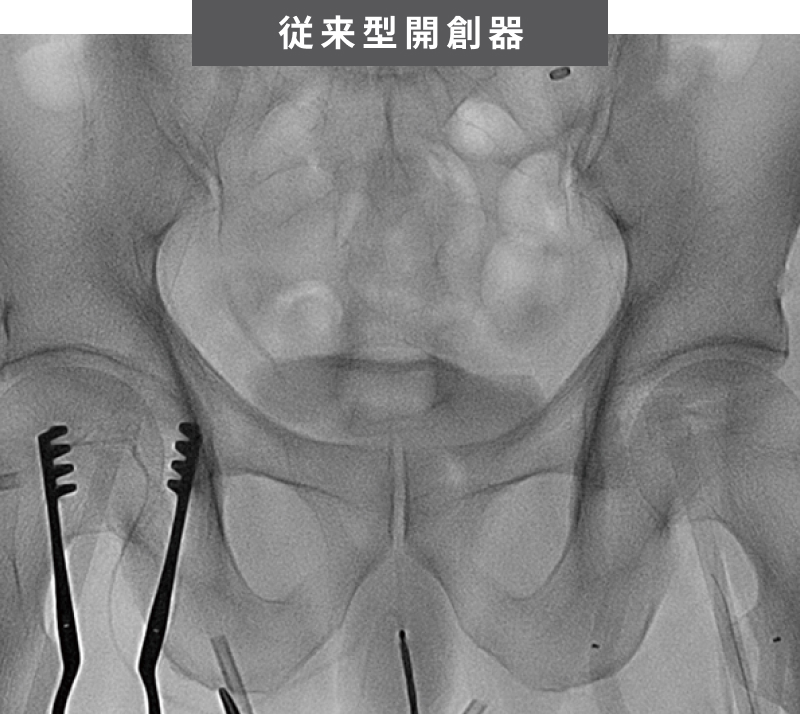

器具がレントゲンに映りこむストレスを開放

消える影。残るのは鮮明な術野。

X線を透過する特殊素材であるPEEK材*1により、開創器の影は術野から消滅。本来見るべき情報だけが、鮮明な画像として現れます。金属の影による重要な情報が隠れてしまうリスクを解消、見えないからこそ、医師の集中力と正確な判断を最大限にサポートします。